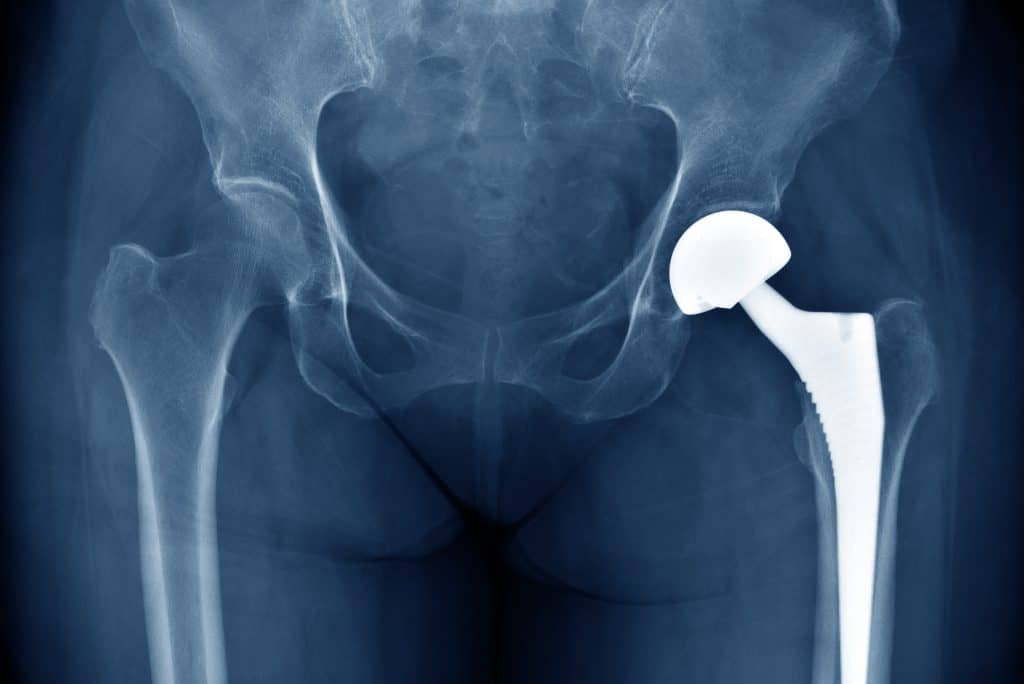

Metal líquido revoluciona combate a infecções em implantes é o ponto central de uma pesquisa da Universidade Flinders, na Austrália, que propõe um biomaterial capaz de reduzir infecções e, ao mesmo tempo, acelerar a integração óssea em cirurgias ortopédicas.

Os cientistas incorporaram nanopartículas de prata-gálio (Ag-Ga) a um andaime biocerâmico 3D de hidroxiapatita. Nos testes, o material apresentou ação antimicrobiana sustentada contra patógenos como Staphylococcus aureus, MRSA e Pseudomonas aeruginosa, principais vilões de próteses de quadril e joelho.

Cerca de 85 000 substituições de quadril e joelho são realizadas por ano na Austrália. A resistência bacteriana torna os antibióticos sistêmicos menos eficazes, enquanto cimentos carregados de fármacos perdem ação rapidamente. A nova solução oferece uma alternativa sem depender de antibióticos, crucial para a segurança de longo prazo dos pacientes.